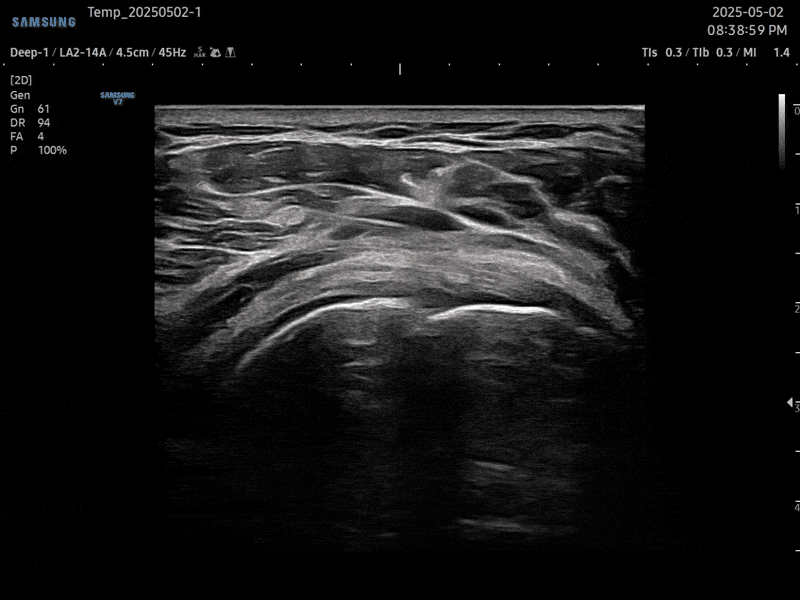

초음파 검사를 통해

오십견 통증의 직접적인

원인을 확인할 수 있습니다.

어깨 관절낭의 관절낭의 염증 정도를 정확하게

파악하여 치료 솔루션을 제시합니다.

01. PDRN 약침

PDRN 약침은 인체의 DNA와 90% 이상 유사한 구조로 세포 증식을 활성화하여

손상된 조직을 복구하는 효과가 뛰어납니다. 초음파를 활용하여 신경을 압박하는

염증을 박리하고 손상된 조직을 재생합니다.